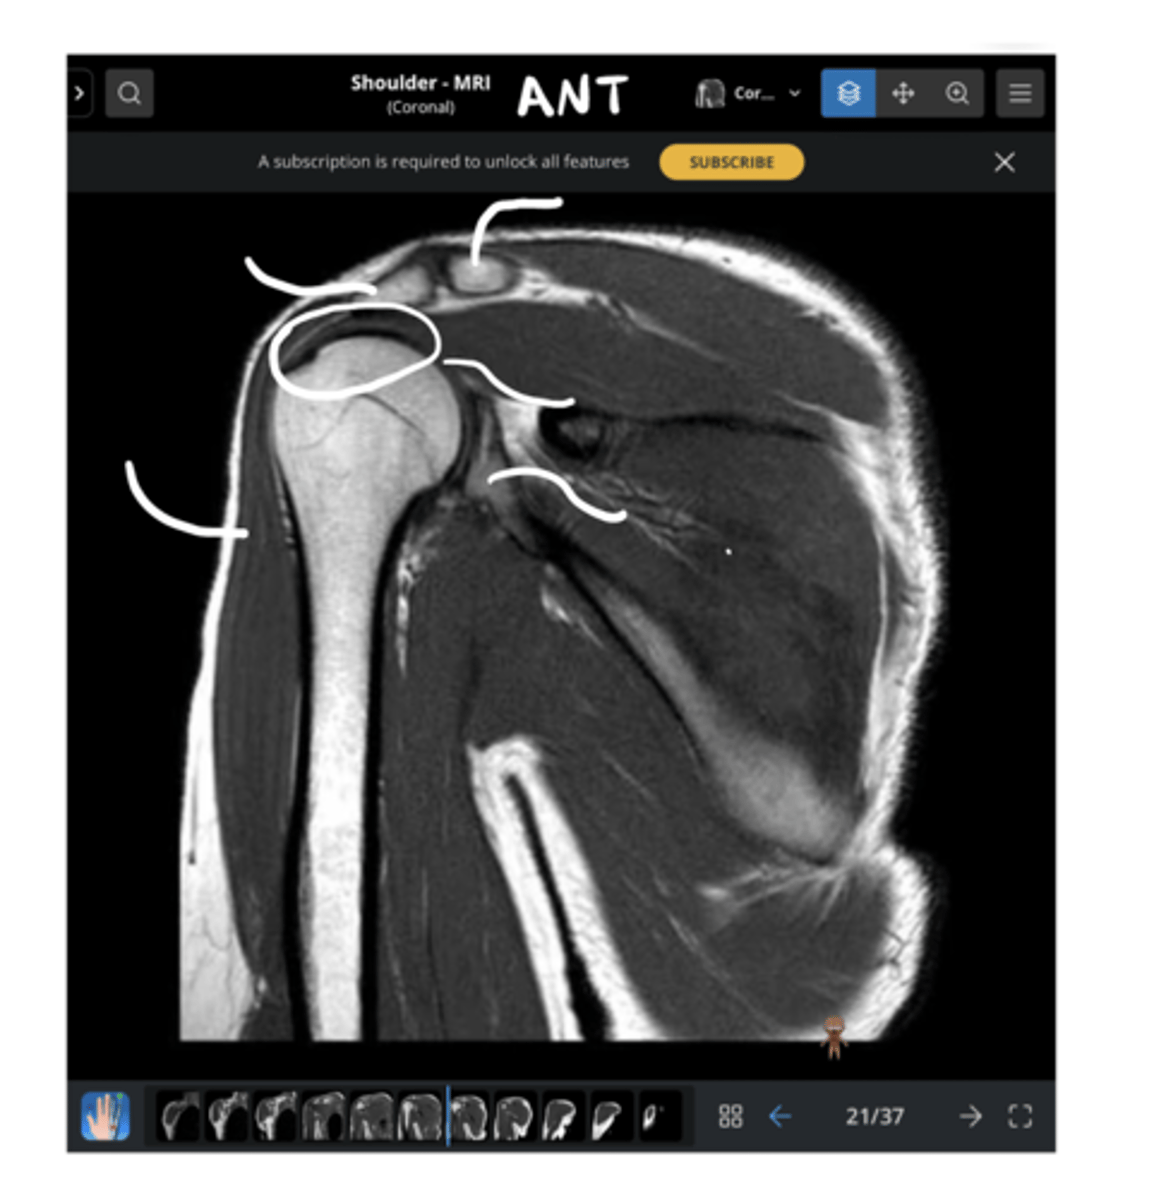

Posterior coronal view of the shoulder -- now, instead of seeing the supraspinatus, we are seeing the infraspinatus

What type of view is this? Anterior vs. posterior? How do you know?

1. Posterior coronal view

2. NO CORACOID

3. Posterior deltoid

1. What view is this image?

2. How do you know?

3. Which structure is being pointed to?

2. NO CORACOID -- spine of the scapula

3. Superior = spine of the scapula, inferior = infraspinatus

3. Which structures are being pointed to?

2. Glenoid

2. Which structure is being pointed to?